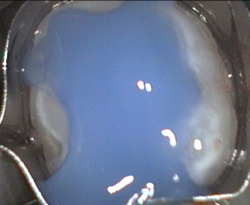

Unusual prevalent but superficial groove pattern on permenant molar after Sealed